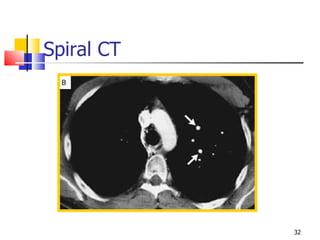

Spiral CT

Tomographic scan showing infarcted left lung,  large clot in right main pulmonary artery

Tomographic scan showinginfarcted left lung, large clot in right main pulmonary artery